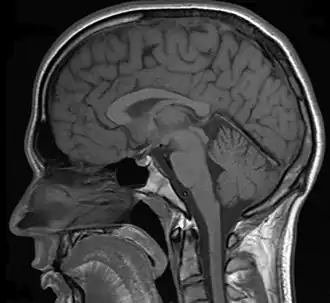

Neuroimaging

Various studies have used MRIs (magnetic resonance imaging) to measure brain activity when individuals detect (or fail to detect) a change in the environment. When individuals detect a change, the neural networks of the parietal and right dorsolateral prefrontal lobe regions are strongly activated.[32][33] If individuals were instructed to detect changes in faces, the fusiform face area was also significantly activated. In addition, other structures such as the pulvinar, cerebellum, and inferior temporal gyrus also showed an increase in activation when individuals reported a change.[33] It has been proposed that the parietal and frontal cortex along with the cerebellum and pulvinar might be used to direct an organism's attention to a change in the environment. A decrease of activation in these brain areas was observed if a change was not detected by the organism.[32] Furthermore, the neurological activation of these highlighted brain areas was correlated with an individual's conscious awareness of change and not the physical change itself.[33]

Other studies using fMRI (functional magnetic resonance imaging) scanners have shown that when change is not consciously detected, there was a significant decrease in the dorsolateral prefrontal and parietal lobe regions.[32] These results further the importance of the dorsolateral prefrontal and parietal cortex in the detection of visual change. In addition to fMRI studies, recent research has used transcranial magnetic stimulation (TMS) in order to inhibit areas of the brain while participants were instructed to try to detect the change between two images.[34] The results show that when the posterior parietal cortex (PPC) is inhibited, individuals are significantly slower at detecting change.[34] The PPC is critical for encoding and maintaining visual images in short term working memory, which demonstrates the importance of the PPC in terms of detecting changes between images.[34] For a change to be detected, the information of the first picture needs to be held in working memory and compared to the second picture. If the PPC is inhibited, the area of the brain responsible for encoding visual images will not function properly. The information will not be encoded and will not be held in working memory and compared to the second picture, thus inducing change blindness.